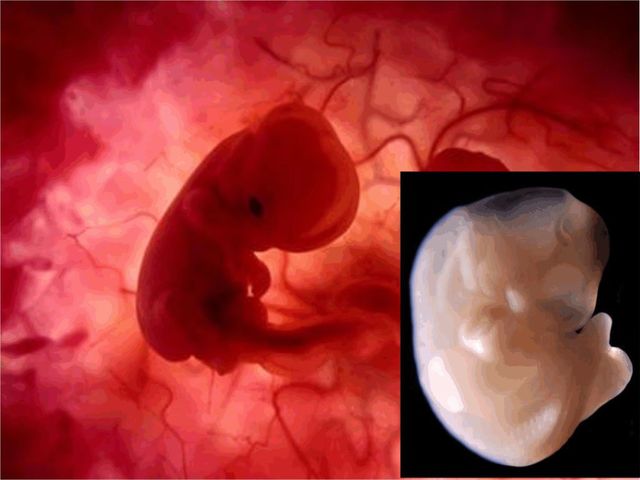

• Semana 8

Semana 8

-El embrión pasa a llamarse feto.

-La placenta es el sistema de alimentación del feto.

-Red de finos capilares.

-Filtra sustancias nocivas.

-Primeros movimientos del feto.

• Semana 9

Semana 9

-El SN se desarrolla y extiende sus conexiones por todo el cuerpo humano.

-Todo el cuerpo del feto empieza temblar.

-La conexión al cerebro aun está en fase de desarrollo.

-El cerebro aún no controla movimientos del feto.

-El cerebro tampoco controla al corazón, los latidos 157 pulsaciones.